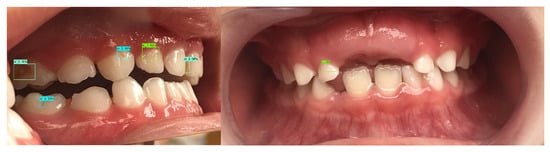

All patients had their teeth cleaned to remove dental plaque and stains. Teeth were cleaned with a low-speed handpiece, polishing brushes (IPC, Boston, MA, USA), Nupro prophy paste (Nupro, Dentsply Sirona, Charlotte, NC, USA) then rinsed with water for 10 s and blown dry for 5 s before taking photos. Intraoral images of the smooth surface of teeth were photographed with an iPhone 7 (Apple, Chicago, IL, USA) with 3 views (central, right lateral, and left lateral view) to cover all teeth. The central view focused on buccal surfaces of incisors (tooth A, B) (Figure 1a,c). The lateral view involved buccal surfaces of teeth on one side (teeth C, D, and E) (Figure 1b,d). Equipment supporting photography were lip retractors (Osung MND Co., Ltd., Houston, TX, USA), intraoral mirrors (DME4G, Osung MND Co., Ltd., Houston, TX, USA), lamp-supported mirror handles, and blow-drying (FF-Photo, Osung MND Co., Ltd., Houston, TX, USA). Finally, 1902 intraoral images from 695 people for training and 750 intraoral images from 250 people for testing were included. All images were exported in JPEG format.

Figure 1.

Central view (a,c) and lateral view (b,d) photos with non-cavitated (in green boxes) and cavitated lesions (in blue boxes) diagnosed by deep learning models (YOLOv3, Faster R-CNN).

A box was created with a code 1, 2, or 3 for each tooth that was suspected to be decayed. Then, the final output label of each photo was the label that included all diagnoses without detection of lesion location (Figure 1).